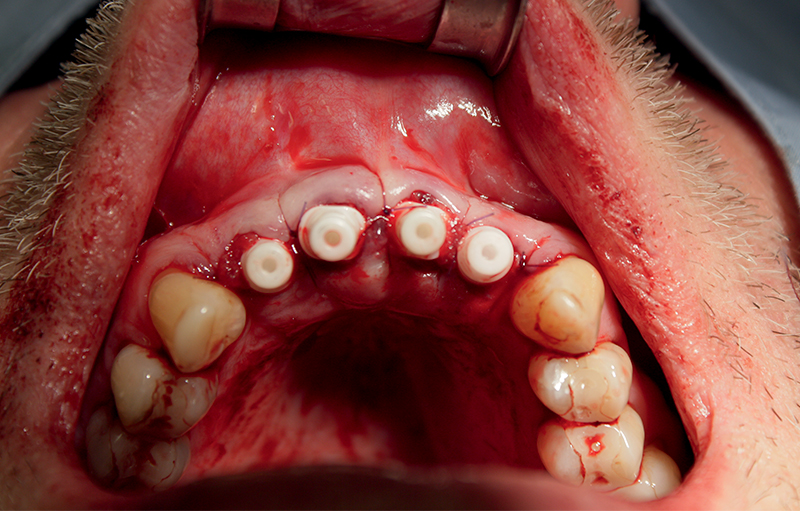

Fig. 2 (caso 1) - Vista clinica occlusale immediatamente dopo l'inserimento degli impianti in zirconia. Impianti SDS ovali nella regione anteriore, posizioni 11 e 21, fixtures classiche nelle posizioni 12 e 22, ed inserimento delle matrici PRF

Caso 1: Un paziente, maschio di 59 anni, si presentava con cisti apicali sugli incisivi centrali e laterali mascellari con trattamento canalare inadeguato. Seguiva posizionamento immediato di impianto in ceramica SDS con carico immediato per un periodo di 2 mesi. (Fig. 1,2).